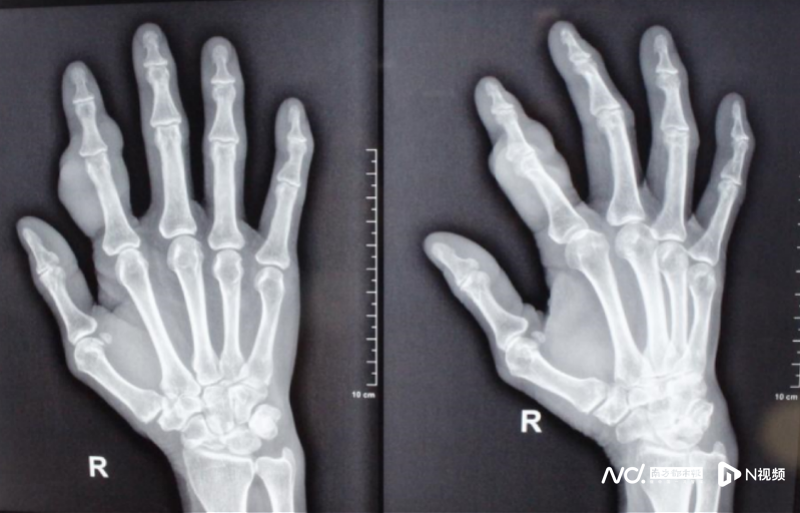

“患者來(lái)就診時(shí),在其指背及雙側(cè)可見(jiàn)大小不一腫塊,腫塊質(zhì)韌,活動(dòng)度差,影響指間關(guān)節(jié)活動(dòng)。初步診斷為腱鞘巨細(xì)胞瘤,術(shù)后病理報(bào)告也明確了這一診斷。”醫(yī)院顯微手外一科、手病專(zhuān)科王小立主任說(shuō)。

術(shù)后食指外形恢復(fù)正常